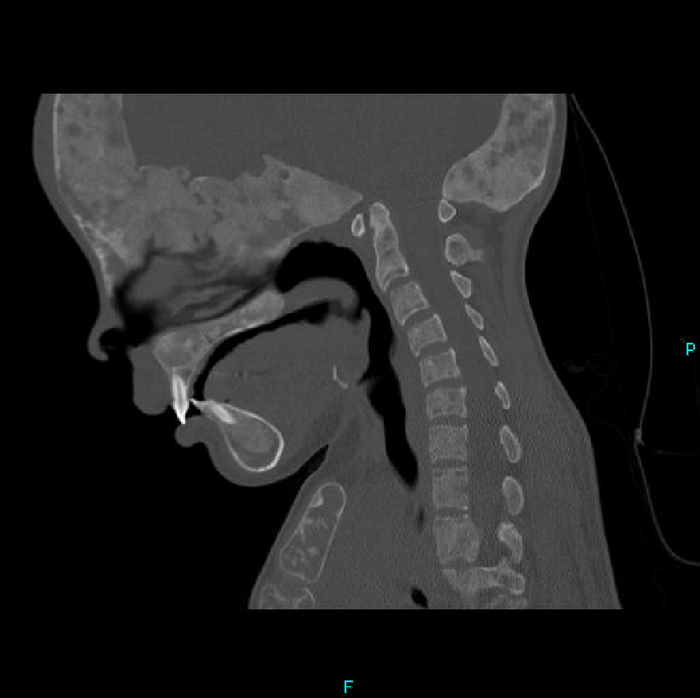

Но вернёмся к случаю: Пациент - девочка, 15 лет. Поступила после ДТП. У нас было проведено КТ-обследование по протоколу политравмы (голова / шея / грудь / живот / таз), где свежих переломов обнаружено не было, но были непонятные леденцы с костями, а именно структура и форма костей со следами старых переломов (грудная клетка и таз с бедренными костями) и, как следствие, их деформацией + следы проведённого остеосинтеза (операция с последующей фиксацией кости тем или иным способом) обоих бедренных костей. Сегодня без пометок / стрелочек, так как картинки говорят сами за себя (всё в костном окне, и всё, что мы видим - кости):

Структура костей напоминала таковую при фиброзной дисплазии (аномалия развития костной ткани с замещением нормальной кости фиброзной тканью, не является опухолью), но, обычно, эти диcплазии возникают в одном месте, т.е. поражают 1 кость (моностотическая форма) и, намного реже, бывают множественные поражения (полистотическая форма), но не всего скелета, как в нашем случае.